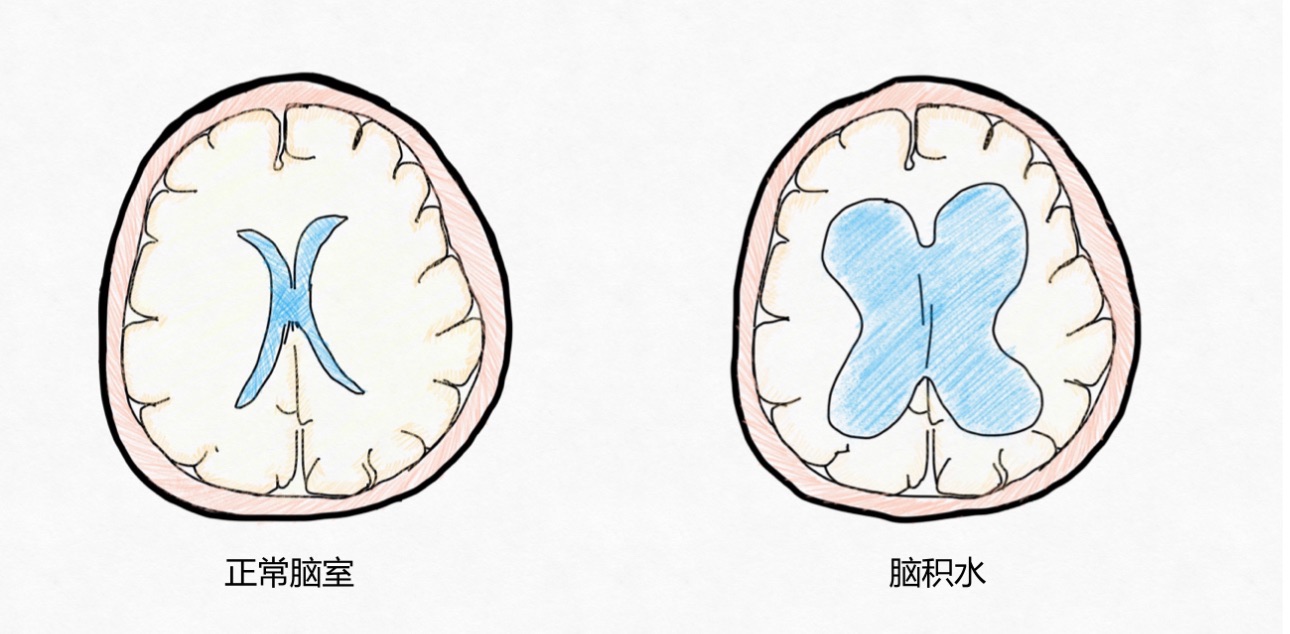

8月龄的多多,是个头有点大的男娃娃。出生的时候他的头就比同龄宝宝大一些,不过家里的老人一点不在意,还非常开心,总是把“头大好呀,聪明呀”挂在嘴边,“你们看看电视上那个大头儿子多聪明呀”。随着月龄增大,家里人开始觉得不对劲了,多多的头围长得快,而且抬头也抬得不好,总是一抬头很快就耷拉下来,也不会翻身,坐不住,最近看东西眼神也不好,还老向下翻白眼。多多妈妈着急了,这该不会有什么问题吧?赶紧抱着多多去了最近的儿童医院看神经外科。医生给多多做了仔细的体格检查,同时做了头颅CT,最后诊断是:先天性脑积水(重度)。看着一脸茫然的妈妈,医生便耐心做起了科普宣传。今天,就让小儿神经外科医生带大家了解一下儿童脑积水吧。 什么是脑积水? 脑积水,并不是说外面的水进入到脑子里面,而是指脑子里面产生的“水”,即脑脊液,积聚的太多了,导致脑室扩张,并常伴有脑内压力的增高,从而产生一些异于同龄正常儿童的表现。

正常脑室与脑积水示意图

为什么会发生脑积水? 正常情况下,脑内是会储存少量的脑脊液,对中枢神经系统起到缓冲、保护、营养、运输代谢产物以及维持正常颅内压力的作用。脑脊液是处于不断的产生、循环和回流的平衡状态,但是当这个平衡被打破时,脑脊液的产生超过了脑子自己本身能够吸收的量,那么脑脊液就可能会积聚太多,从而引起脑积水。根据病因,儿童脑积水可以分为先天性脑积水和继发性脑积水(后天性)。

脑脊液产生与吸收不平衡时会发生脑积水

脑积水的宝宝会有哪些表现呢? 脑积水的表现主要取决于发病时间(相对于颅缝闭合的时间)、颅内压增高的速度及持续时间以及是否伴有相关的结构异常。 1. 婴儿和儿童轻度脑积水可能没有症状,通常是偶然检查发现的; 2. 颅缝闭合前的脑积水宝宝:最常见的表现就是头围增大,也就是前面提到的“大头娃娃”,头太大,颈部肌肉比较薄弱,以至于出现抬头不稳或者不能抬头,与同龄宝宝相比,有可能存在发育迟缓,比如说到了该抬头的月份不能抬头、不能翻身、不能坐起、不能站立等等,有些宝宝甚至还会出现发育倒退、行为改变,比如容易激惹等; 3. 年龄较大的儿童:因为颅缝闭合了,少了颅缝和囟门能够缓冲的空间,所以脑积水多的情况下,会出现明显的颅内压增高的表现,包括清晨头痛明显、恶心、呕吐、行走不稳、行为改变等等; 4. 急性脑积水:除了头痛、呕吐,还可能会出现意识状态的改变,包括昏睡、嗜睡等; 5. 外观上的异常:婴幼儿的脑积水比较容易从外观上发现,包括头围增大,头皮静脉很明显、曲张或者显露、囟门张力高、“落日征”(眼睛不能上视,总是下翻,露出眼白部分)等。 怀疑脑积水应该做哪些检查呢? 1. 定期监测头围:如果婴儿在孕期产检有脑室增宽、出生时有头围增大,连续监测头围的测量值总是在标准曲线以上,表明头部生长过度,应怀疑婴儿有脑积水,要做进一步的检查。 2. 颅腔B超:对于新生儿和小婴儿,即前囟还没有闭合的宝宝,可以选择做个颅腔B超,非常便捷,一般不需要镇静。 3. 头颅CT或者头颅MRI:对于疑似脑积水的年龄较大的婴儿和儿童,应该进行头颅CT或者头颅MRI检查,除了评估脑积水的程度,还可以发现结构异常或者肿瘤等后天因素。 4. 眼底检查评估视乳头水肿:脑积水引起颅压增高还会导致视乳头水肿、视物不清楚、视力下降等情况,对于脑积水的年龄较大的儿童,可以做眼底检查评估是否存在视乳头水肿,也可以侧面反应脑积水导致颅压增高的情况。